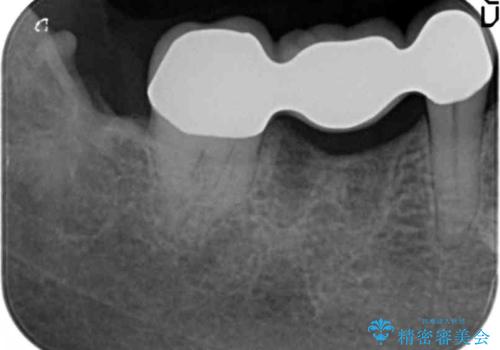

抜歯後十分に歯肉の治癒を待ったのち、ブリッジによる補綴治療を行いました。

痛みが出るのが怖い・外科手術は避けたいとのご希望でブリッジをご希望されました。

ブリッジの自然な見た目と咬み心地にご満足頂けました。

メタルボンドクラウン(外側はセラミック、内側はメタル)では舌側の歯頚部がメタルの場合が多いのですが、すべてセラミックで覆うフルベイク仕上げでオーダーし、審美性を追求しました。

クラウンの種類:メタルボンドクラウン エコノミー フルベイク